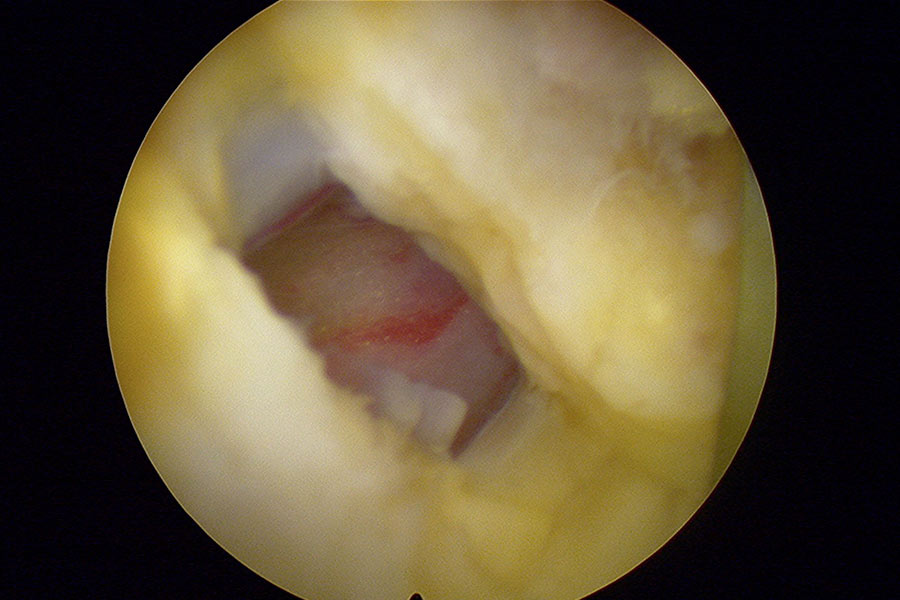

La hernia se eliminará con una técnica de endoscopia mínimamente invasiva, con una incisión de unos 2 mm, es decir, que dejará una cicatriz mínima en el paciente y que garantiza una recuperación mucho más rápida que en el caso de las intervenciones convencionales..

hernia-discal-mononivel-endoscopia-de-columna